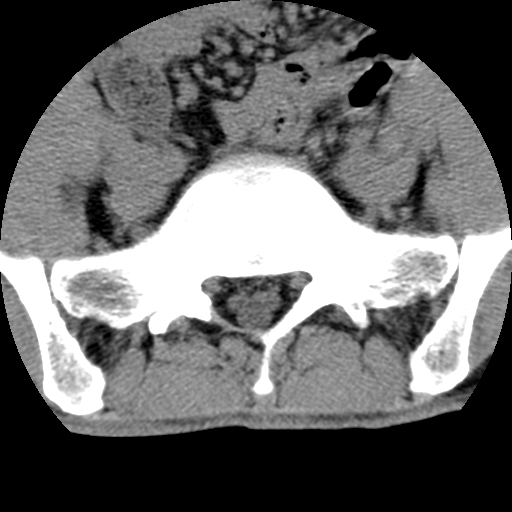

标题: CT16890:男,腰背痛.

男,腰背痛

本人诊断1tb2包虫,请会诊

1)右侧竖脊肌稍低密度肿块伴钙化(性质待定),不排除肿瘤可能;建议行进一步检查。2)腰椎间盘突出。

1.右侧竖脊肌软组织肿块伴团块状钙化,首先考虑血管瘤可能性大;建议行进一步检查;2。腰椎间盘突出。